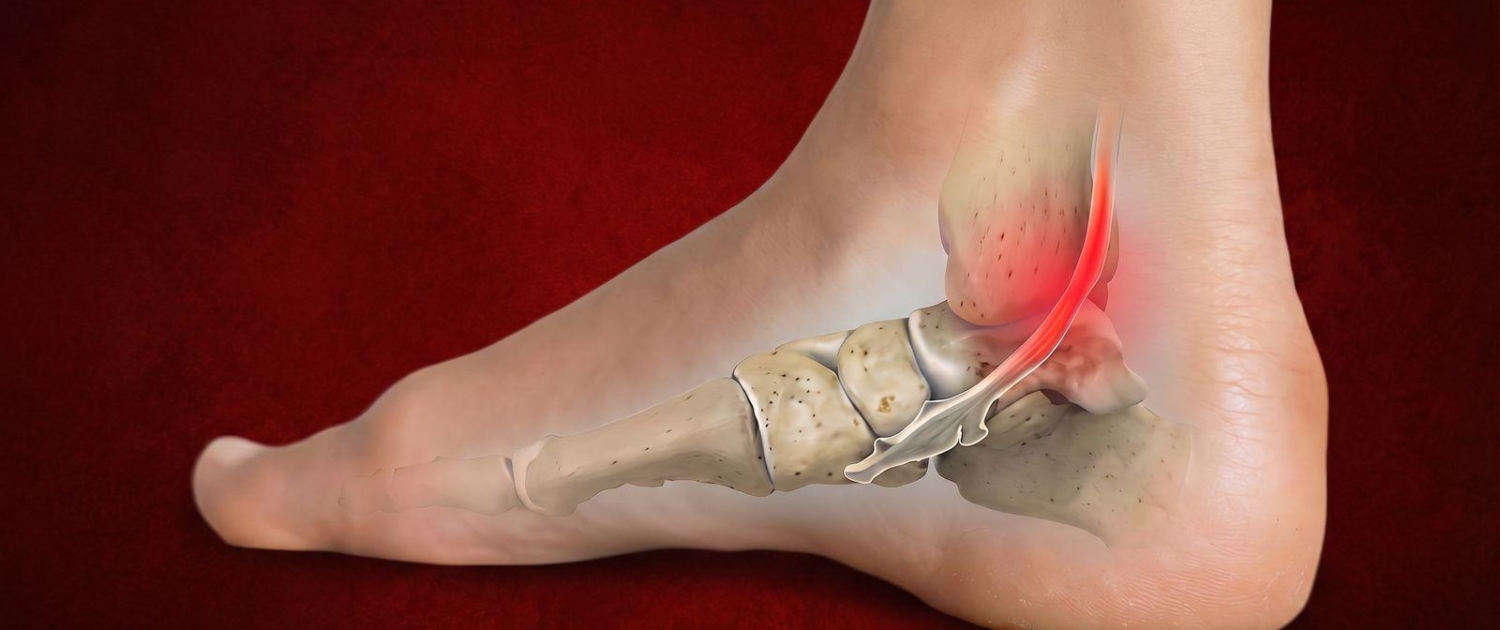

Tibialis posterior je mišić potkoljenice čija tetiva prolazi iza unutarnje „koščice“ (medijalnog maleola) gležnja te se hvata za kosti stopala (navikularnu i medijalnu kuneiformnu kost). Ima ključnu ulogu u pravilnoj biomehanici stopala. Pojednostavljeno, zašto je toliko važna za kretanje i trčanje:

Tendinitis je stanje u kojem se tetiva koja povezuje mišić s kosti, upali i postane bolna kao posljedica preopterećenja. Kod sportaša tendinitis često nastaje kao rezultat kombinacije više biomehaničkih čimbenika: prekomjerne pronacije, slabosti ekstenzora kuka, smanjenog opsega pokreta u gležnju (pokret prstima prema gore), bježanja koljena prema unutra tijekom aktivnosti te neadekvatne tehnike. Važnu ulogu imaju i promjene u opterećenju, poput nagle promjene u intenzitetu treninga, povećanje pretrčanih kilometara , promjena podloge i/ili obuće. Uglavnom je zahvaćena samo jedna noga.